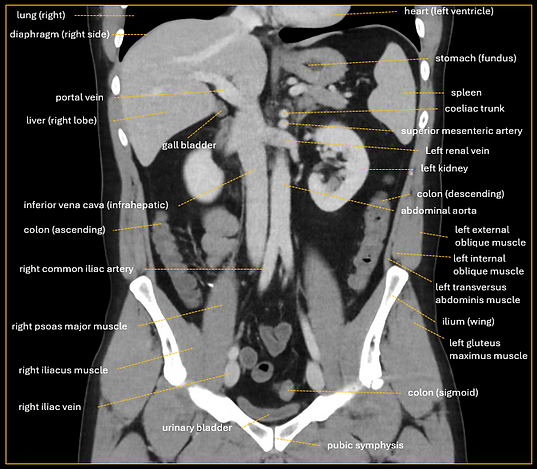

FIGURE 1. EXAMPLE ANATOMICAL ANNOTATION OF A CORONAL ABDOMINAL CT IMAGE IN A SUBJECT WITHOUT PATHOLOGICAL FINDINGS.

Annotation is the precise identification and labeling of anatomical structures in (medical) images. MATHELIOS ANNOTATIONS delivers anatomically accurate, consistent annotations, tailored to your research or development needs, with careful consideration of anatomical variability and clinical context.